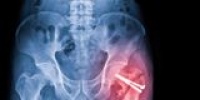

В середине мая 2025 года 74-летний мужчина перенес операцию после перелома шейки бедра. После лечения он смог восстановиться и снова начал ходить. Однако в ноябре того же года ситуация резко ухудшилась: после очередного падения его вновь доставили в приемный покой ОКБ №2. Несмотря на жалобы на боль и ухудшение состояния, врачи не выявили серьезных повреждений и отправили пациента домой.

Через два дня мужчину снова привезли в больницу, на этот раз он уже не мог самостоятельно передвигаться. Родственники настаивали на дополнительном обследовании, но врачи не обнаружили перелома и вновь предложили выписку. Только после настойчивых просьб дочери был проведен повторный рентген, который выявил сложный перелом бедренной кости со смещением. Пациента экстренно госпитализировали, но его состояние продолжало ухудшаться.